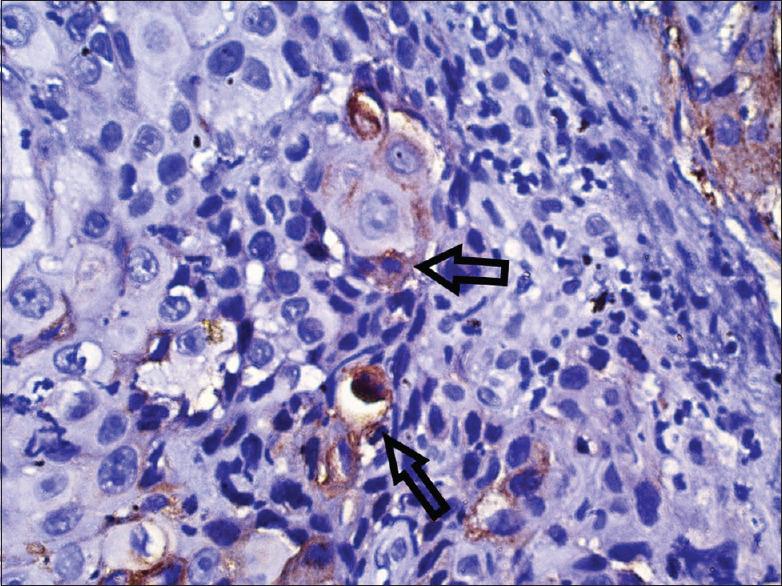

Necrotizing ulcerative periodontitis (NUP) is a painful and debilitating condition seen mostly in an immunocompromised state. Although squamous cell carcinoma (SCC) on gingiva is not uncommon, its presentation as a benign necrotizing lesion on gingiva is rare. Such presentations may lead to delayed diagnosis and poor prognosis. This report describes a case of a 34-year-old male presenting clinically with NUP around mandibular posterior teeth. Clinical features were misleading, but the histological findings established the diagnosis of well-differentiated SCC. Immunohistochemistry also showed features of epithelial-mesenchymal transition with decreased expression of E-cadherin and increased vimentin expression showing local invasion and metastasis. The patient was referred to the oncology department for evaluation of possible metastasis and further management of carcinoma.

坏死性溃疡性牙周炎(NUP)是一种主要见于免疫功能低下状态的疼痛性且使人衰弱的病症。虽然牙龈鳞状细胞癌(SCC)并不罕见,但其表现为牙龈上的良性坏死性病变则较为罕见。此类表现可能导致诊断延迟和预后不良。本报告描述了一例34岁男性患者,临床上表现为下颌后牙周围的NUP。临床特征具有误导性,但组织学检查结果确诊为高分化SCC。免疫组织化学还显示出上皮-间质转化的特征,E-钙黏蛋白表达降低,波形蛋白表达增加,提示局部侵袭和转移。该患者被转诊至肿瘤科,以评估可能的转移情况并对癌症进行进一步治疗。